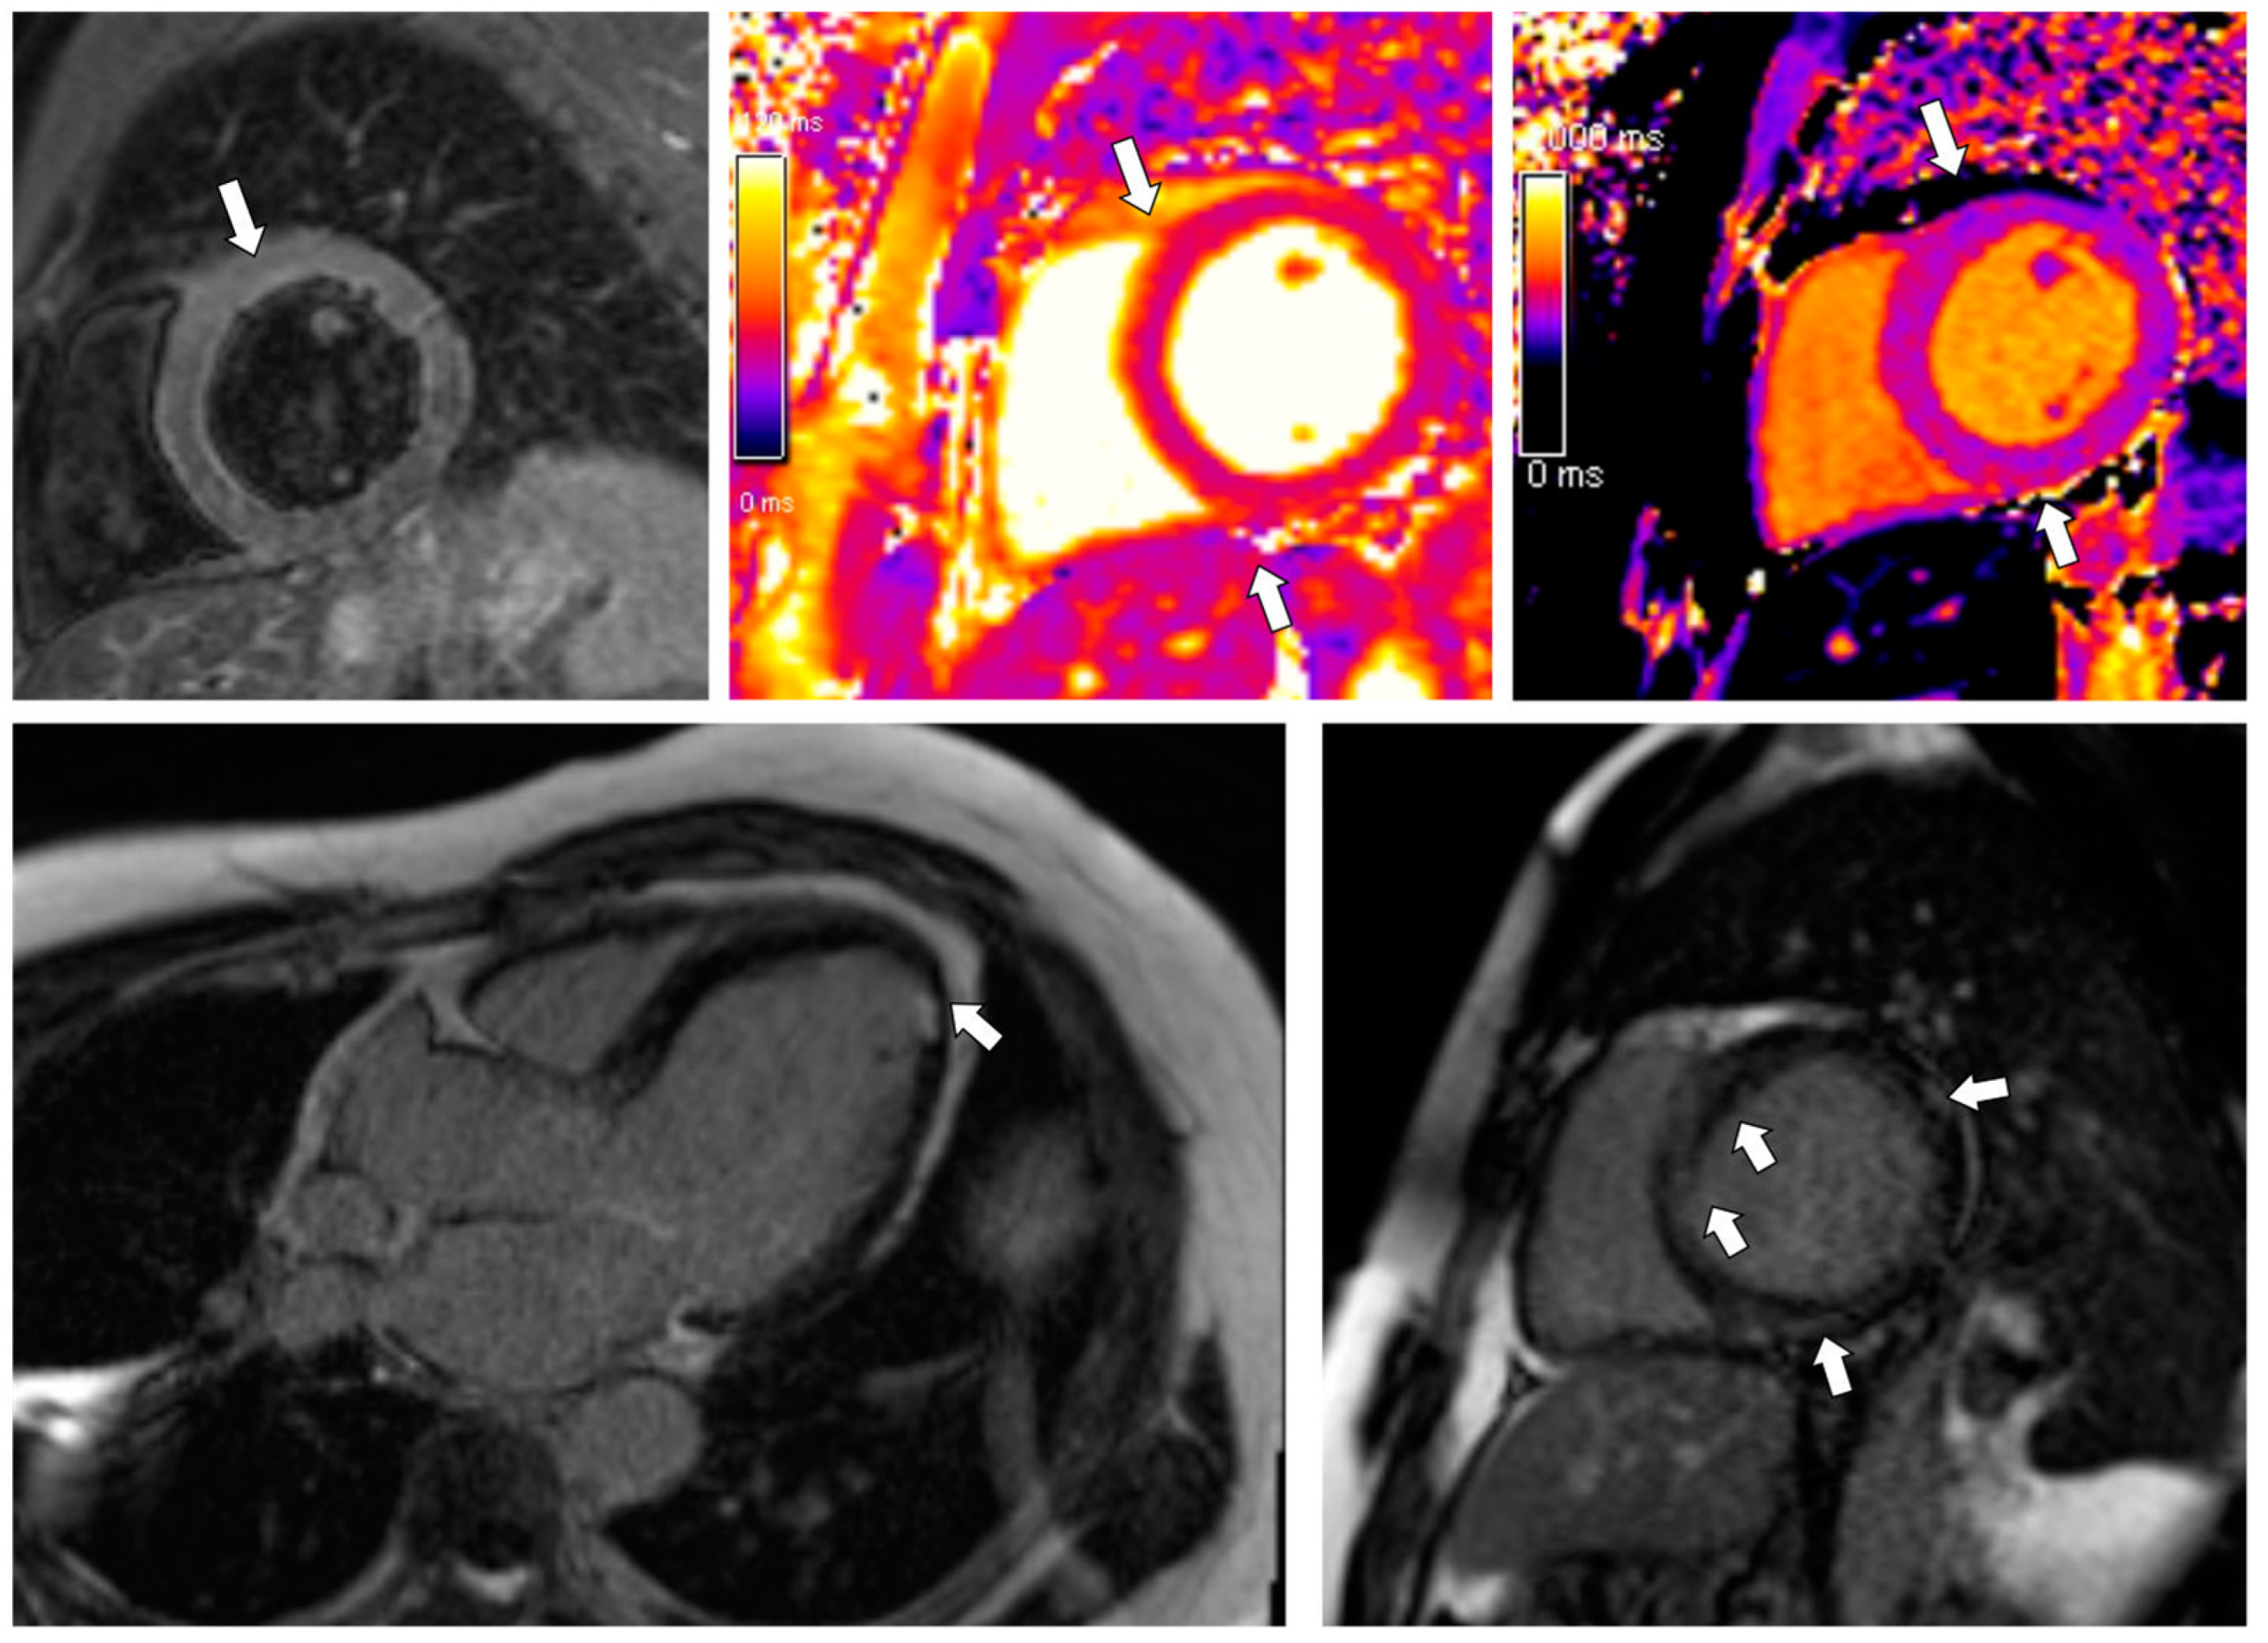

3.3. Case 3

| Case 1 (CMR 1) | Case 1 (CMR 2) | Case 2 | Case 3 | |

|---|---|---|---|---|

| LVEDV (mL; normal 83–207) | 206 | 227 | 489 | 215 |

| LVEDVI (mL/m2; normal 47–107) | 99 | 110 | 242 | 106 |

| LVEF (%; normal 51–76) | 49 | 53 | 14 | 26 |

| LVSV (mL; normal 55–127) | 100 | 121 | 67 | 55 |

| RVEF (%, normal: 42–72) | 53 | 47 | 21 | 34 |

| Native T1 (ms; normal 993 ± 21) | not measured | 971 | 1014 | 1012–1080 |

| T2 (ms; normal 44 ± 2.4 ms) | not measured | 47 | 46 | 48 with local increase subepicardially up to 53 ms |

| LGE (segments) | subepicardial

| not detected | intramural-subepicardial

| intramural—subepicardial

|

| ECV (%; normal 25.3 ± 3.5) | not calculated | 26 | 30 | 30 |